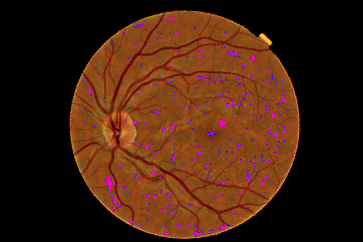

Refer to caption

Figure 4: Pixel probability maps obtained from the final CNN for a different number of epochs. In initial epochs, the probability map include low probabilities of MA (depicted as green spots), in the subsequent epochs, the medium and high probabilities are in blue and purple respectively.